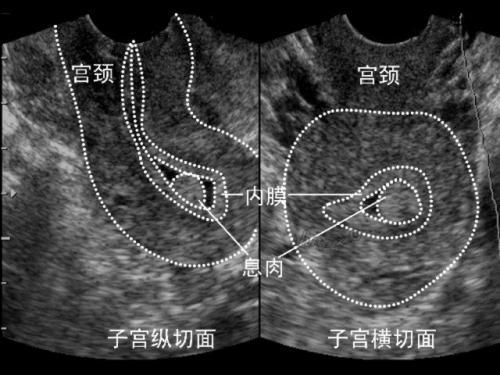

这里我简单地做了一张示意图,向大家展示一下相关的病理。

左侧是腺肌症保宫手术之前的子宫状貌,子宫比较大,比较饱满,最明显的是子宫的肌肉特别的厚,中间星星点点的病灶在上面广泛分布,里面的凸槽部位便是子宫腔,触角状的东西便是子宫内膜,而依附于子宫内膜之上,触角的尖头部位那些增粗成团的赘生肉便是息肉。

右侧是腺肌症保宫手术后的子宫,子宫腺肌症病灶剔除后,子宫肌肉就变得非常薄了,不需要大量的营养物质供应了,里面增粗增厚的血管自然也就没了,这时候不可能再出现大量蒂状的息肉了。所以通过剔除子宫腺肌症病灶组织,改善子宫肌肉状态,能够有效地解决息肉问题。这是一个前后紧密相连的病理关系,只要本源上的问题解决了,与之相枝连的问题自然也就迎刃而解、不攻自破了。